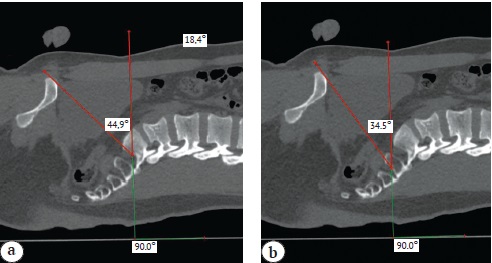

The S1 outlet angle was plotted with the apex at the midpoint of the superior margin of the S1 sacral foramen, with the ray coinciding with the vertical line drawn to the horizontal surface of the table on which the patient was lying, and the ray connecting the apex of the angle and the superior edge of the pubic bone (Fig. 2 a). The S2 outlet angle was plotted with the apex at the midpoint of the superior margin of the S2 sacral foramen, with the ray coinciding with the vertical line drawn to the horizontal surface of the table on which the patient was lying, and the ray connecting the apex of the angle and the superior edge of the pubic bone (Fig. 2 b).

Fig. 2. S1 outlet view angle (а); S2 outlet view angle (b)